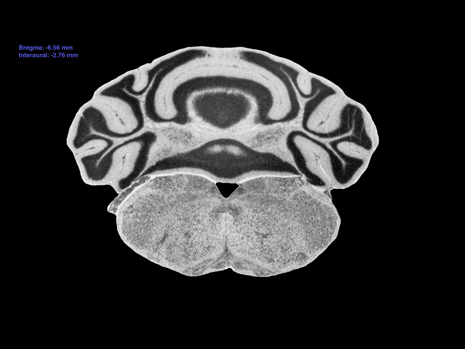

C57BL/6J Atlas - Section 33

Interaural: -2.76 mm

Bregma: -6.56 mm

Mouse Brain Section